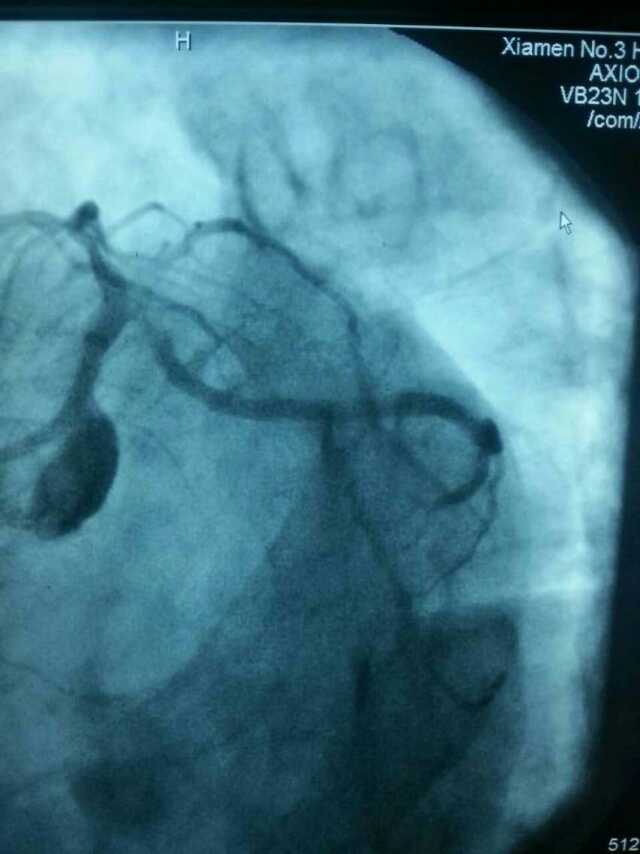

3月20日,家住翔安的庄先生为感谢91club 心血管内科的医护人员在第一时间对他的病情给予明确诊断,并及时采取有效治疗措施,让他的心脏病很快得到康复回家。特地送来一面写着“德医双馨,妙手回春”锦旗以表达他们满满的感激之情。